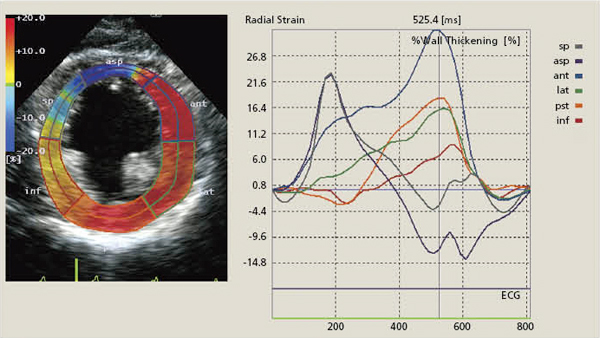

こうしたストレインやrotationの値はカラーコード化され,パラメトリックイメージングとして心筋のBモード像に重畳して表示することが可能である。図5に,実際の2DTによるストレイン解析・表示例を示した。また,ASE,AHAで定められているセグメントごとの各パラメータの平均値についての時間変化をグラフ表示することも可能である。

図5 パラメトリックイメージングとグラフ表示(radial strain)